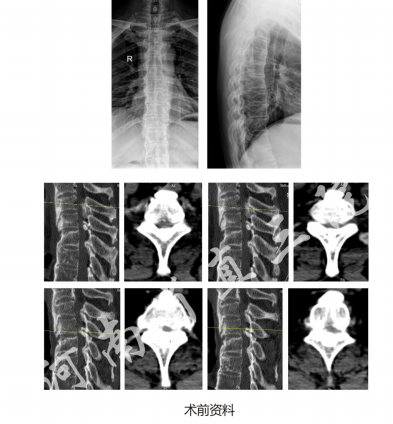

病例

UBE下三节段上胸椎椎管减压术

患者,男,54岁;

主诉:双下肢无力、麻木4月,加重半月

既往史:患者4月前无明显诱因出现双下肢麻木、无力,未在意未系统检查治疗;半月前上述症状呈进行性加重,站立和行走困难。一般情况可。

主要体格检查:痉挛步态,平剑突以下皮肤感觉减退,会阴部皮肤感觉减退,双下肢肌力IV级,肌张力增高,膝腱反射亢进,踝反射亢进,踝阵挛阳性。双侧Babinski征阳性。

诊断:胸椎管狭窄症(T1/2、T2/3、T3/4,黄韧带骨化)

手术方案:UBE下T1-4椎管减压术